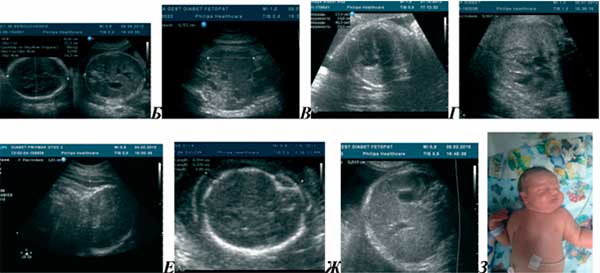

От чего у плода может быть

От чего у плода может быть 119 фото